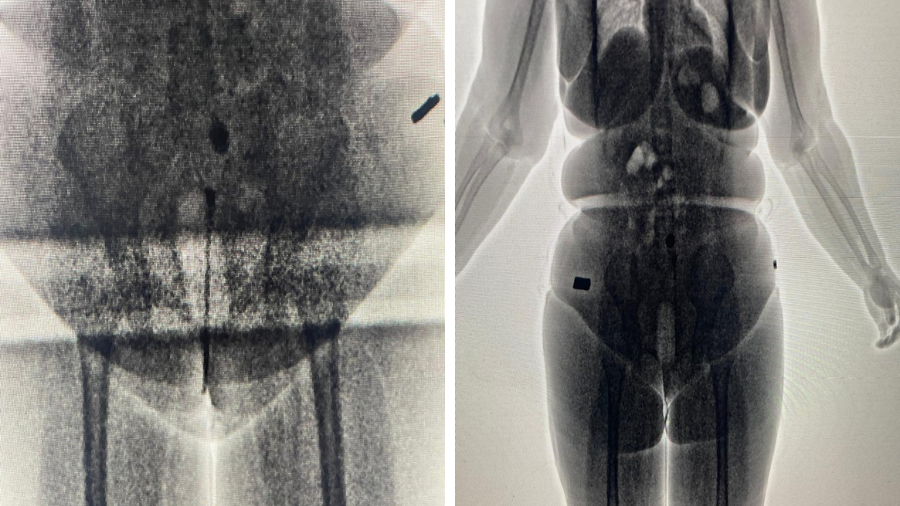

A apreensão foi realizada graças ao Body Scan, scanners corporais utilizados na vistoria. Durante a passagem pelo equipamento, foram detectados objetos suspeitos nas genitálias das visitantes, sendo que uma das drogas estava introduzida no corpo.

Ao todo, cerca de 100 gramas de substâncias ilícitas foram impedidas de entrar no presídio. Uma das mulheres carregava 45 gramas, enquanto a outra portava 47 gramas.